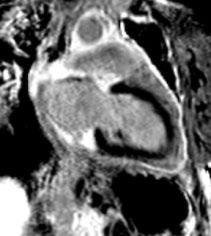

Gastric GIST shows an intermediate pattern of enhancement, while small bowel GIST shows marked arterial phase enhancement. ‘Tumour vessel’ sign, a feature of small bowel GIST due to early venous return and prominence of the draining vein, helps in tracing the origin of the tumour. A nodule within the mass is a sign of recurrence.1 Treatment of choice for resectable GIST is surgery, although neoadjuvant imatinib is given to reduce the tumour size, and postsurgery imatinib is administered to prevent recurrence of the disease for at least 3 years. In case of metastasis or recurrence, imatinib is a first line drug.4,10,11,20

CONCLUSION

Although CT is the modality of choice for GIST, it is imperative for a radiologist to be wellacquainted with various other non-cross section imaging, such as radiographs, small bowel series, and ultrasound, to increase the level of confidence in radiological diagnosis before histopathology and immunohistochemistry confirms it.

Creative Commons Attribution-Non Commercial 4.0 ● April 2024 ● Radiology 91 Case Report

References

1. Inoue A et al. Gastrointestinal stromal tumors: a comprehensive radiological review. Jpn J Radiol. 2022;40(11):1105-20.

2. Levy AD et al. Gastrointestinal stromal tumors: radiologic features with pathologic correlation. Radiographics. 2003;23(2):283304.